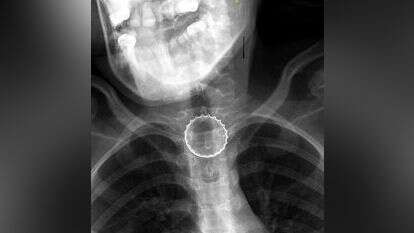

במיון ילדים עברה הנערה בירור מקיף ויסודי ע"י צוות בראשות ד"ר עלי ח'טיב, מומחה ברפואת ילדים, ובין השאר בוצע לה צילום רנטגן, בו התגלה גוף זר בוושט. הנערה הוכנסה לחדר ניתוח, שם - באמצעות ציוד אנדוסקופי ייעודי - הוצא מצינור הוושט פקק של בירה קורונה ע"י צוות ממחלקת אף אוזן גרון וניתוחי ראש-צוואר, בניהולו של ד"ר אייל סלע. הנערה אושפזה להשגחה למשך יממה ושוחררה במצב טוב.

ד"ר נתנאל איזנבך, רופא מתמחה במחלקת אף אוזן גרון, סיפר כי במהלך ההליך הניתוחי התברר, כי מעל לגוף הזר הצטברו שאריות מזון שונות, דבר שהקשה על תהליך הוצאת הפקק.